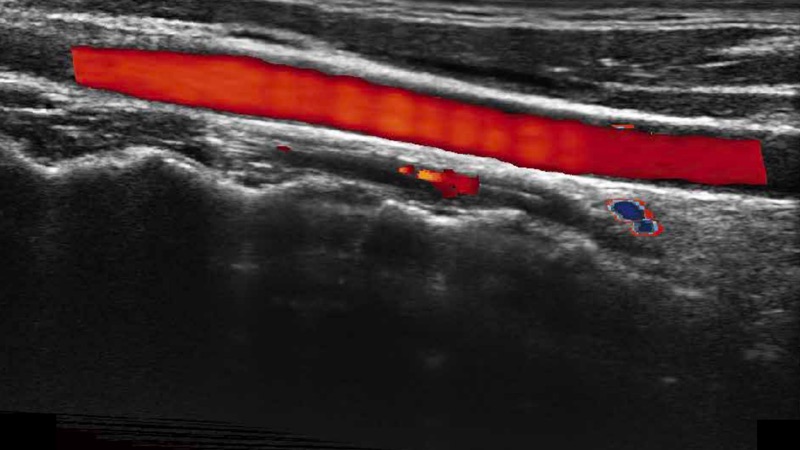

凸陣、線陣和相控陣探頭進行實時掃描時,開啟擴展成像模式,可以擴展超聲圖像視野,以便更完整地查看大的病灶或組織器官的解剖結構。

通過色彩血流和實時寬景相結合,可觀察到完整的靜脈或動脈的血流,方便醫(yī)生檢查。實時掃查過程中,如有任何操作失誤也可以很容易地進行回掃擦除,而不會中斷掃查。